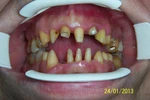

Diş ve Diş eti hastalıkları

Diş Eksikliği

Diş Çürükleri

Diş Eti Kanaması

Kırık Diş

Lezyonlu (Enfekte) Diş

Diş Kırıkları